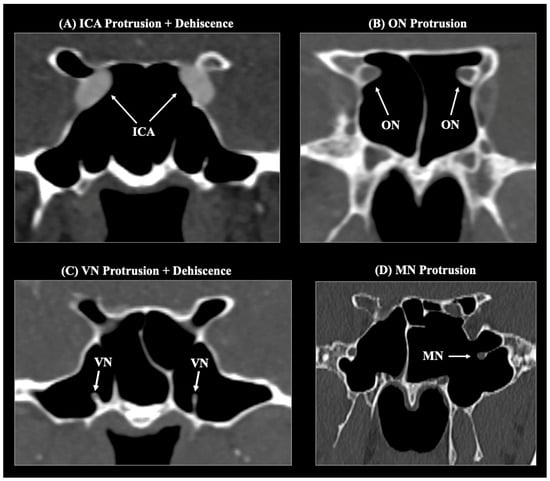

Background/Objectives: The sphenoid sinus (SS) exhibits marked morphological variability, influencing the relationship of critical neurovascular skull base structures. This study aimed to characterize sphenoid sinus pneumatization (SSP) patterns and assess their impact on the course of the internal carotid artery (ICA), optic nerve (ON), Vidian nerve (VN), and maxillary nerve (MN) within a Greek adult population. Methods: A retrospective analysis of 253 adult skull base computed tomography (CT) scans was performed. The degree and direction of SSP were classified according to established radiological criteria. Anterior, lateral, and posterior extensions were evaluated. The course of adjacent neurovascular structures was categorized as typical, protruding, or dehiscent. Associations between pneumatization types and neurovascular variants were analyzed. Results: The sellar complete type was the predominant SS pattern (63.2%), followed by sellar incomplete (27.7%) and presellar (8.7%) types; agenesis was rare (0.4%). Posterior (63.6%) and lateral (46.6%) extensions were most common. Lateral and posterior pneumatization significantly correlated with protrusion and/or dehiscence of adjacent neurovascular structures, particularly the ICA, ON, and VN. LW extension was strongly associated with ON protrusion (96%), while PP and full-lateral extensions correlated with VN protrusion (56.1% and 79.9%, respectively). No significant sex- or side-related differences were identified. Conclusions: SSP demonstrates extensive morphological variability that significantly affects the anatomical course and osseous coverage of neighboring neurovascular structures. Comprehensive preoperative CT evaluation of SS anatomy is essential for planning endoscopic transsphenoidal and extended skull base procedures to minimize the risk of neurovascular injury. Full article

Figure 1